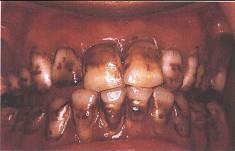

问题 关于氟斑牙,下列哪个说法是错误 ( )

选项 A.又称斑釉牙 B.深层釉质含氟量是表面釉质的11倍左右 C.饮用水是摄人氟的最大来源 D.慢性氟中毒患者可有骨骼增殖性变化 E.氟主要损害釉质发育期牙胚的造釉细胞

答案 B